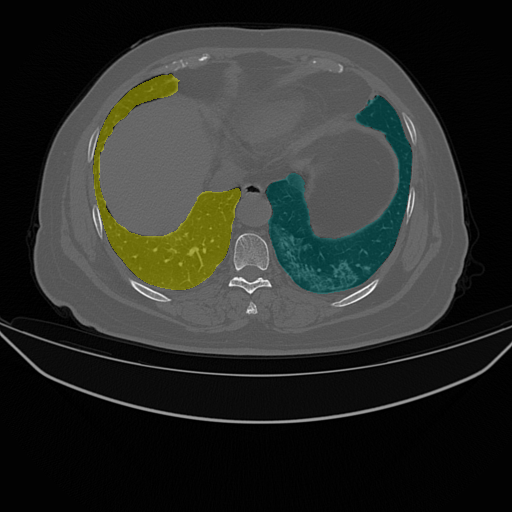

| Lung Segmentation (COV, 2019) Left lung (Cyan) Right lung (Yellow) | ![]() |

| (e) CT slice | (f) FGSM | (g) PGD | (h) Ours | |

While recent studies of adversarial attacks mainly focus on natural images, the research of adversarial attacks in the medical image domain is desired as there are significant differences between two domains. Beyond regular RGB cameras, there are various types of medical imaging equipments (e.g., Computed Tomography (CT) scanners, ultrasound transducers and fundus cameras) to generate dramatically different images. Fig. 1 shows three examples where an image captured from fundus camera is in (a), an image captured from the CT scanner is in (e) and an endoscopic video frame is in (i). As can be seen in the figure that these three images have little in common. The huge data variance across different modalities of medical images brings more challenges to develop a technology that works for all the modalities. In addition, existing investigations on medical adversarial attacks are limited. In Finlayson et al. (2019), adversarial examples are shown to deteriorate the diagnosis accuracy of deep learning based medical systems. These medical attack methods are mainly based on those from natural images (e.g., Fast Gradient Sign Method (FGSM) (Goodfellow et al., 2014) and Project Gradient Descent (PGD) (Madry et al., 2017), which are insufficiently developed for different types of medical data. As shown in Fig. 1, the adversarial examples generated by FGSM and PGD do not consistently decrease the network’s performance in (b), (c), (f), (g), (j) and (k). The data variance in (a) and (e) leads to the inconsistent attack results by existing methods.

We evaluate the proposed method on three medical image analysis tasks including diabetic retinopathy grading, artefact detection, and lung segmentation. The diabetic retinopathy grading is to classify fundus images into predefined categories for diabetes status estimation. The artefact detection is to detect specific artefacts like pixel saturations, motion blur, and specular reflections in the endoscopic images. Lung segmentation is to segment lung region from the whole CT slice. The medical data in one task is significantly different from that in others.

We use two datasets for diabetic retinopathy grading. One is the APTOS-2019 (APT, 2019) dataset with 3,662 fundus images. The other is a large-scale Kaggle-DR (Kag, 2015) dataset where we randomly select 11,000 fundus images from its original training set. Both APTOS-2019 and Kaggle-DR contains five defined categories. For artefact detection we use EAD-2019 (EAD, 2019) dataset with 2,500 images collected from endoscopic video frames and annotated artefact regions with seven defined categories. These detection images focus on multiple image modalities (i.e., gastroscopy, cystoscopy, gastro-oesophageal and colonoscopy), and are captured in multi-resolution with multi-modal (i.e., white light, fluorescence, and narrow band imaging). For lung segmentation, we use the COVID-19 dataset (COV, 2019) where there are 20 CT scans for lungs infected by COVID-19.